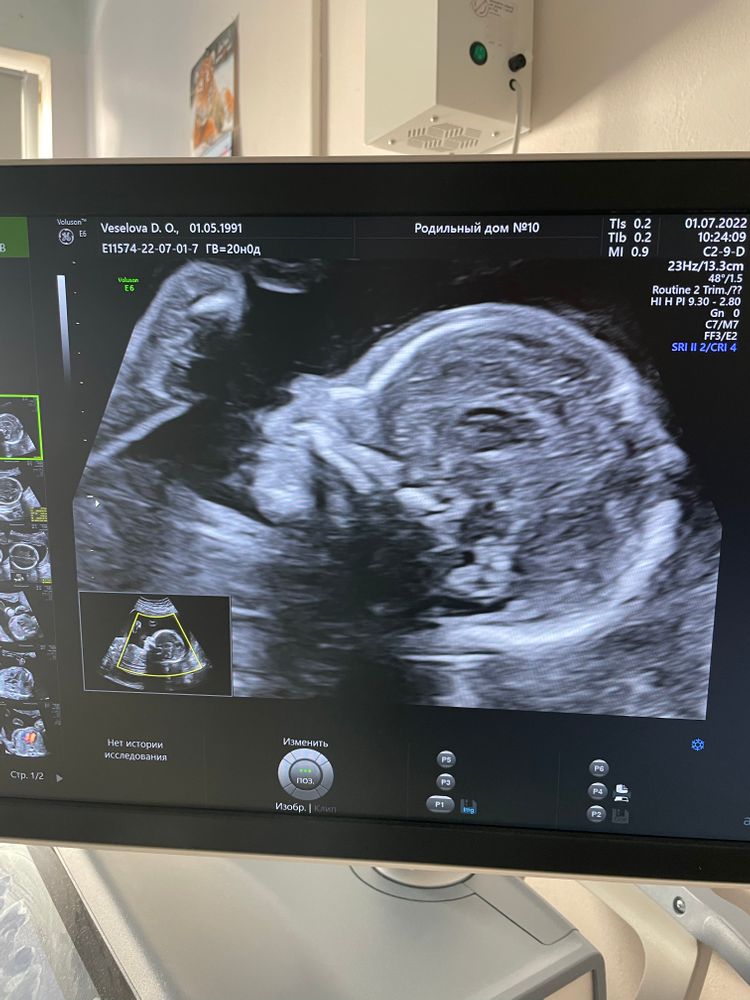

2 скрининг , нам уже 20 недель 🤰🏼🌸